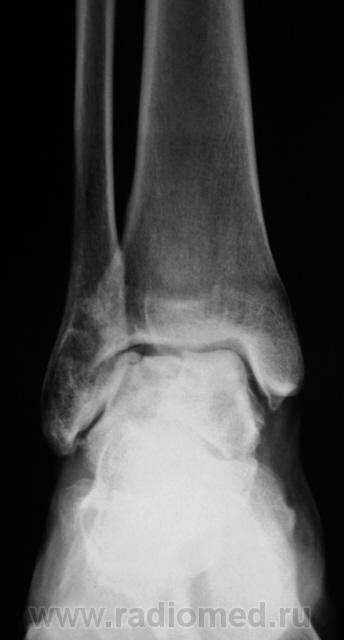

Пациент направлен на рентгенографию голеностопного сустава с диагнозом ДОА.

После внутрисуставного перелома вероятность доа оччень высока. Колгда была травма?

Травма была два года тому.

Похоже  на  остеохондропатию  блока  таранной  кости  +   ДОА.

А присутствует линейный (или лентовидный, я их путаю) остеопороз, а это признак острого процесса.

+ за лентовидный остеопроз...

Будем думать, что некроз блока таранной кости не такой уж и асептический, какая-то инхвекция там есть.

Посттравматический артроз с кистовидной перестройкойлатерального мыщелка Субхондральное уплотнение исужение суст. щелей естьИ неконгруэнтность большеберцового эпифиза к таранной маленько просматривается?